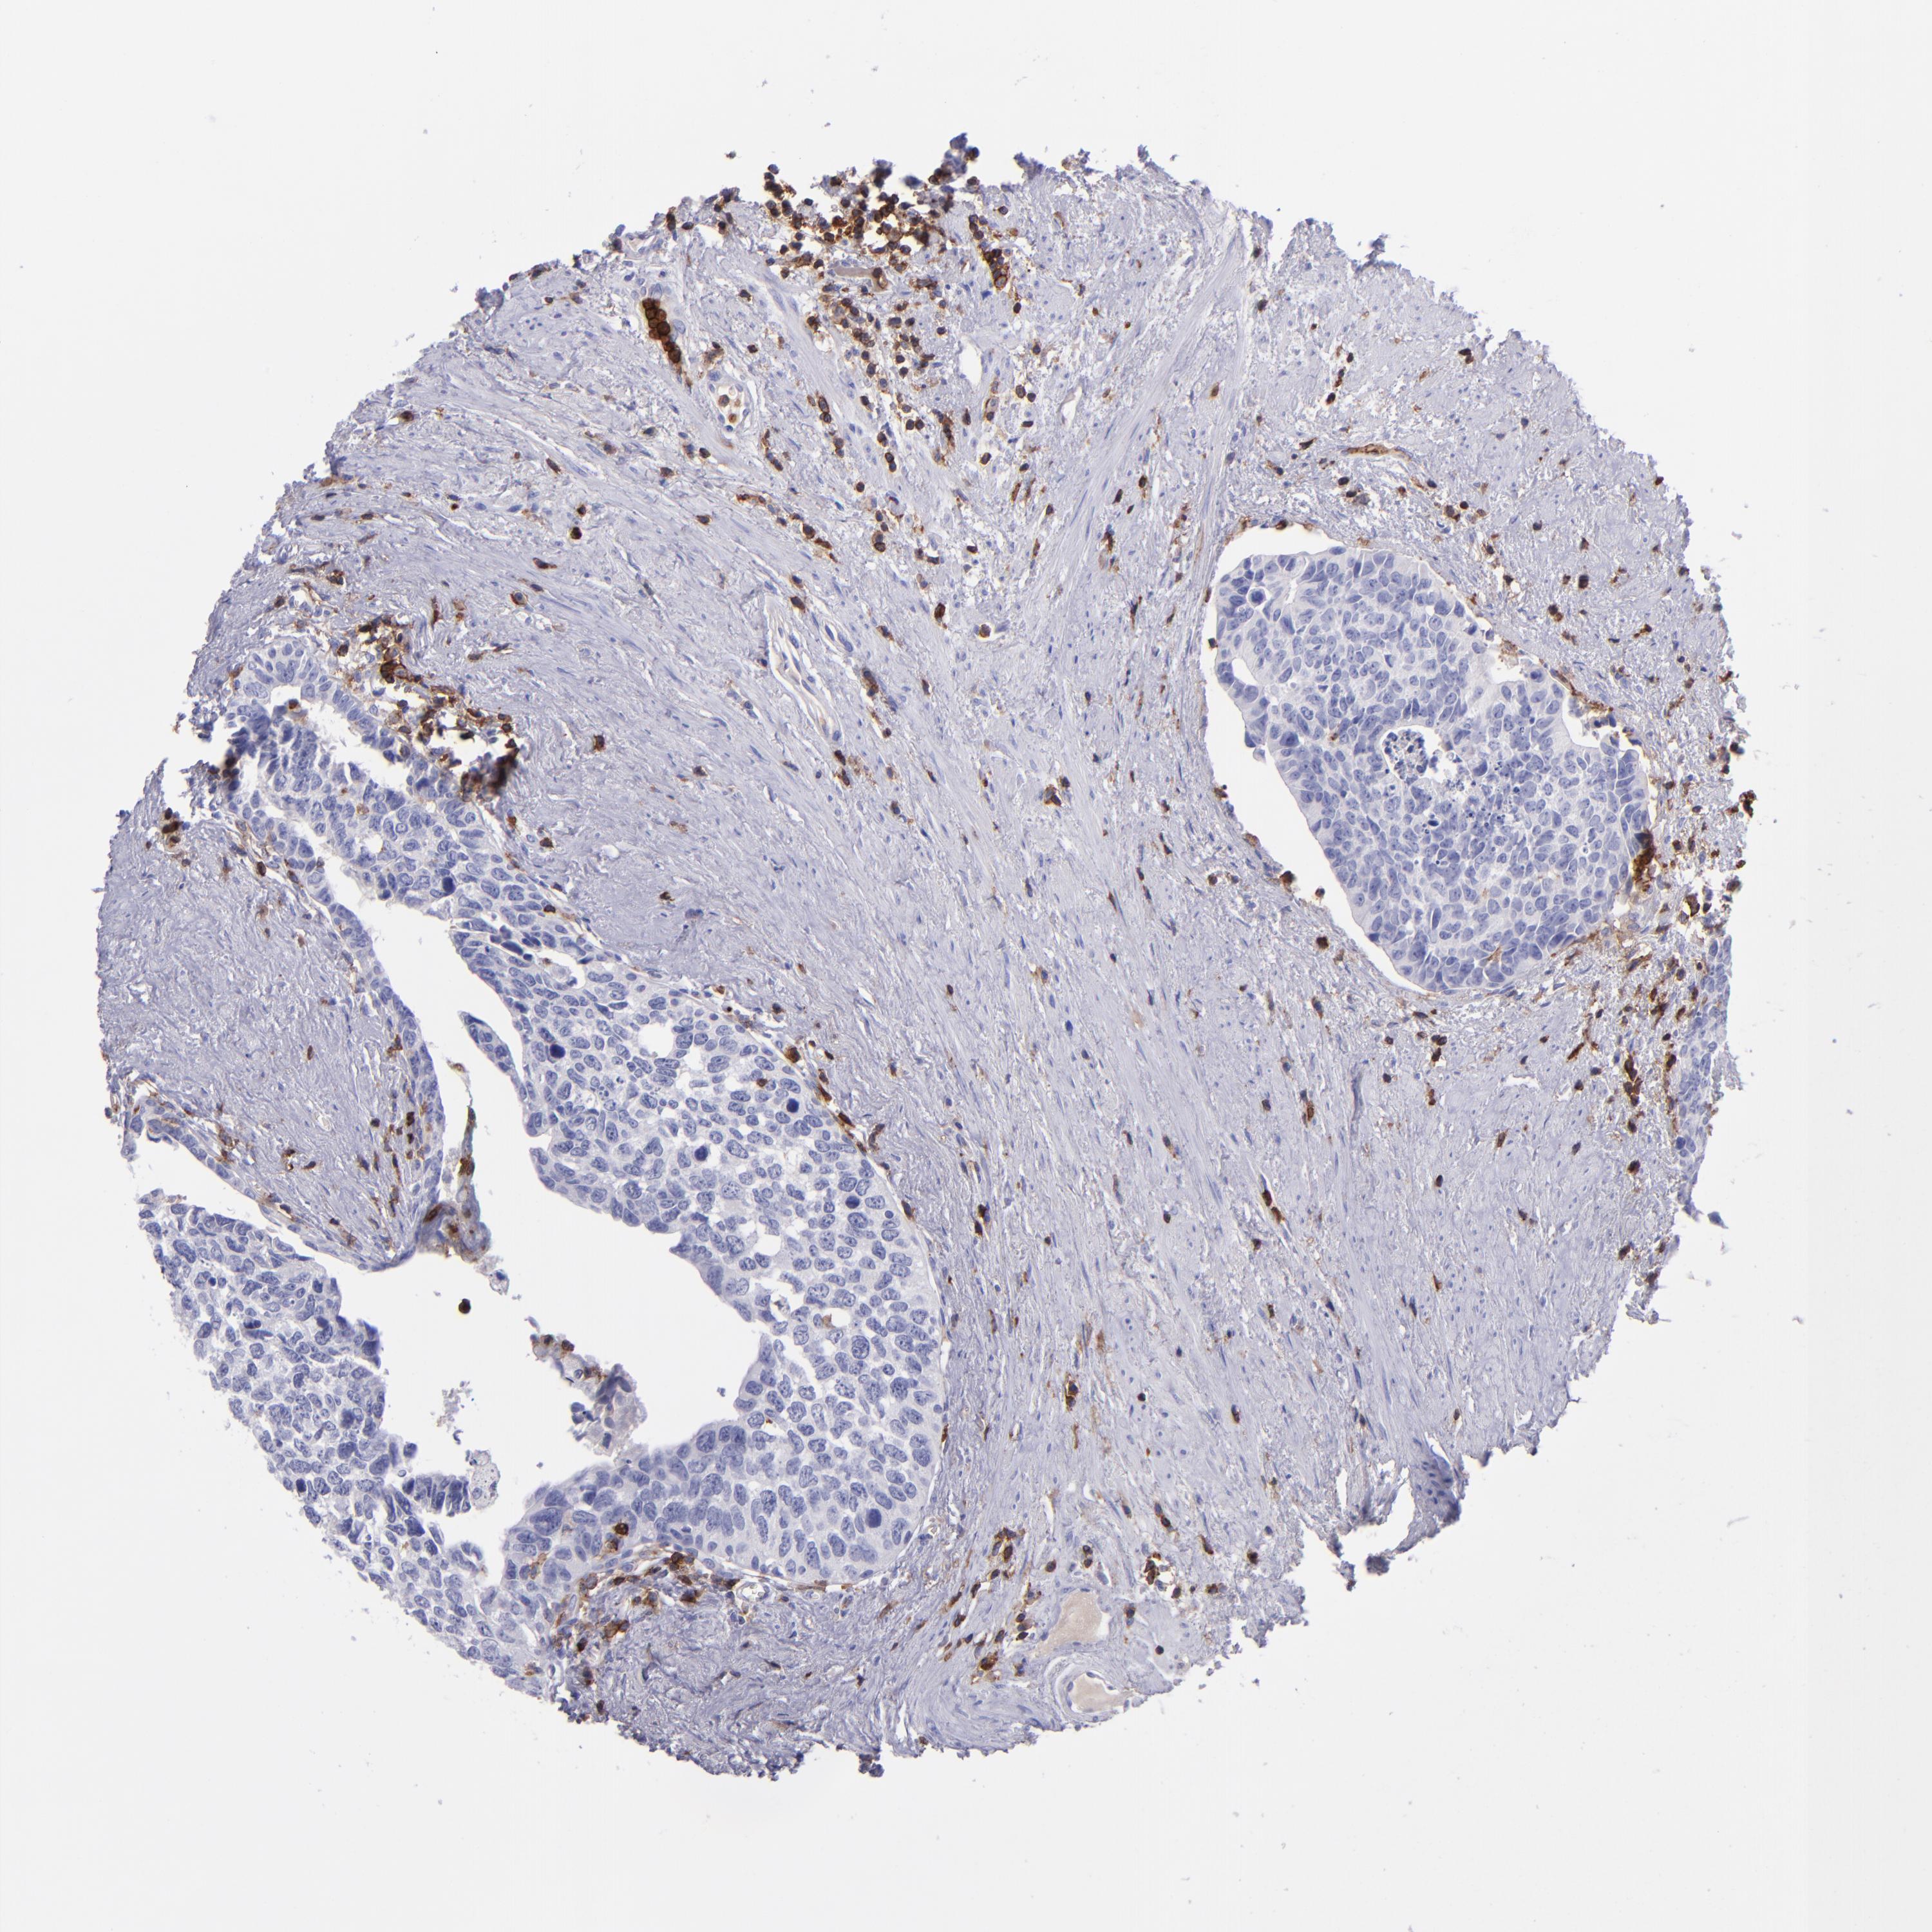

UROTHELIAL CANCER - Protein expressioni

A mouse-over function shows sample information and annotation data. Click on an image to view it in a full screen mode. Samples can be filtered based on level of antibody staining by selecting one or several of the following categories: high, medium, low and not detected. The assay and annotation is described here.

Note that samples used for immunohistochemistry by the Human Protein Atlas do not correspond to samples in the TCGA dataset.

Antibody stainingi

Antibody staining in the annotated cell types in the current human tissue is reported as not detected, low, medium, or high, based on conventional immunohistochemistry profiling in selected tissues. This score is based on the combination of the staining intensity and fraction of stained cells.

Each image is clickable and will lead to virtual microscopy that enables deeper exploration of all samples and also displays staining intensity scores, fraction scores and subcellular localization as well as patient and tissue information for each sample.

Antibody CAB002498

Staining

High

Medium

Low

Not detected

Intensity

Strong

Moderate

Weak

Negative

Quantity

>75%

75%-25%

<25%

None

Location

Nuclear

Cytoplasmic/membranous

Cytoplasmic/membranous,nuclear

Urothelial carcinoma, High grade

Urothelial carcinoma, Low grade

Adenocarcinoma, NOS